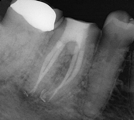

Treatment Examples

Conventional Endodontic Treatment with Post and Core Coronal Restoration

Conventional Endodontic Treatment/Retreatment with Prefabricated Bonded Post and Core

All Treatment performed by Dr. Brian A. Christopherson